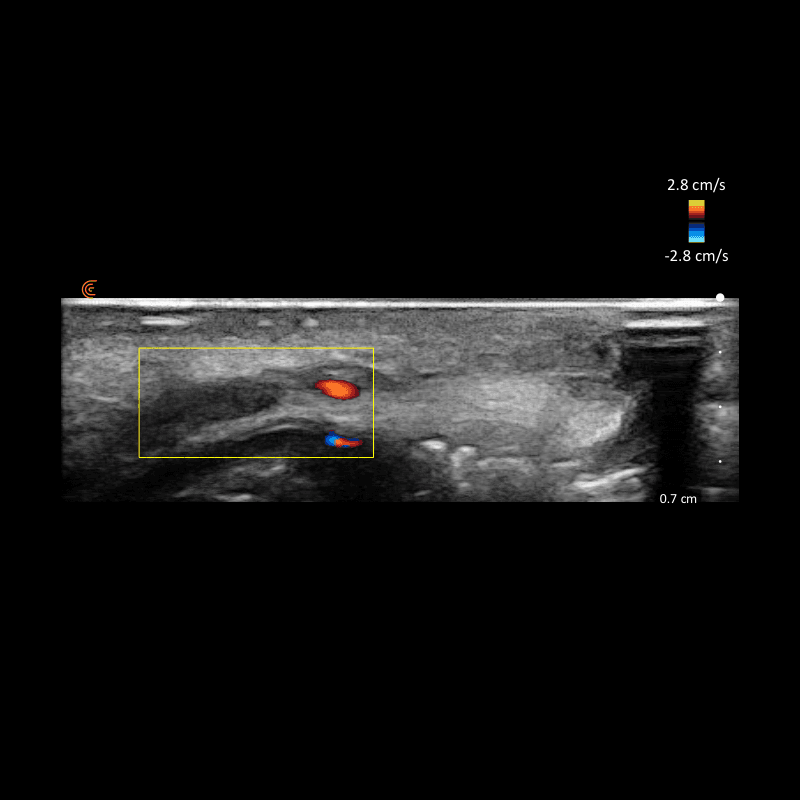

Durch den Einsatz von hochauflösendem Ultraschall ist es möglich, die jeweilige Gesichtsregion live zu „scannen“ und kritische Strukturen wie Arterien, Venen und bestehende Fillerdepots exakt zu identifizieren. So kann die Injektion nicht nur sicherer, sondern auch gezielter durchgeführt werden.

Ein grosser Vorteil der ultraschallgestützten Technik ist das deutlich reduzierte Risiko für intravaskuläre Injektionen – eine der schwerwiegendsten Komplikationen bei Fillerbehandlungen. Indem Blutgefässe sichtbar gemacht und konsequent umgangen werden, lassen sich Gefässverschlüsse, Nekrosen oder andere unerwünschte Reaktionen weitgehend vermeiden.

Gleichzeitig ermöglicht der Ultraschall eine präzise Platzierung des Fillers in der richtigen anatomischen Schicht – subkutan, supraperiostal oder intradermal. Dadurch lässt sich das gewünschte Ergebnis natürlicher und harmonischer erzielen, und auch die Haltbarkeit kann optimiert werden.